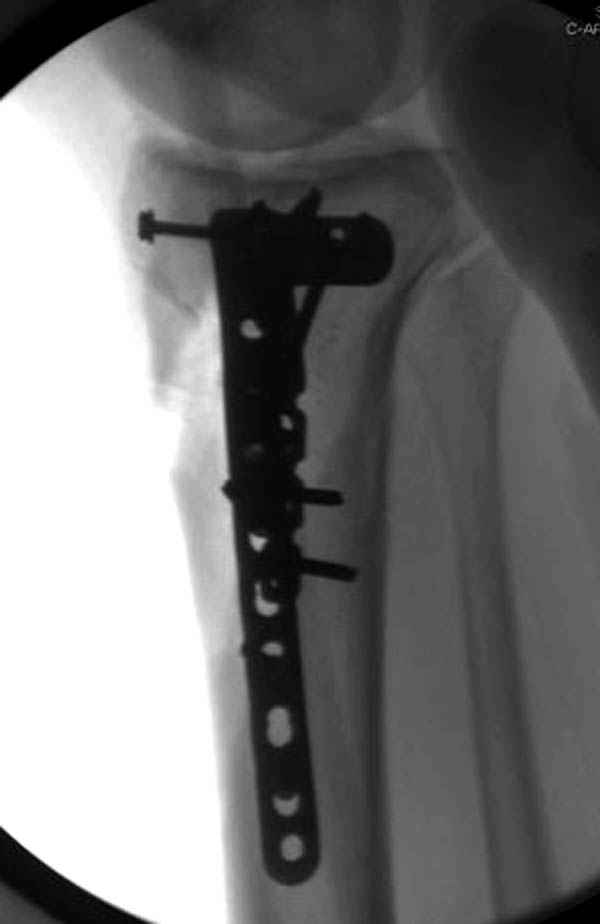

Пациенту сделали КТ - ухитрились сделать на шине Белера (не давал положить прямую ногу) - срезали передний отдел. Планируется на пятницу (24.12) на операцию - синтез длинной мыщелковой LCP-пластиной Synthes :). Отек ближе к слову умеренный (окружность голени +4 см по сравнению со здоровой). КТ и снимок на вытяжении прилагаются.

Уважаемые коллеги! В прошлую пятницу больной прооперирован - как и планировалось мыщелковая LCP от ChM. Малоинвазивно не получилось - один большой доступ :(. (но с минимальным скелетированием б/б кости). Наружный мыщелок собрали, но по контролю видно, что задне-медиальный отдел метаэпифиза смещен. Фиксировать не стали (?). 4-е сутки после операции - по м/тканям без проблем. Дополнительная иммобилизация синтетическим тутором.

P. S. перелом диафиза на контроле не совсем захвачен, но проблем там нет. Приношу извинения за низкое качество Р-грамм - выполнены на сканере (фотоаппарат не работает :)) .

Трудно поверить, что разрекламированная Ортопедическая школа Восточной Украины позволяет такие странные снимки? На прямом снимке сохранен общий контур плато, но не известна судьба импрессии суставной поверхности. На полубоковой?, оставлен без репозиции задне-медиальный отдел, и навряд ли после такой фиксации можно удовлетвориться результатом.

Такая ситуация характерна для многих, когда принимается ошибочное решение, т.е пытаются фиксировать одним имплантом переломы двух мыщелков. Латеральная пластина приемлема только для тех случаев, когда сохраняется интактным медиальный диафизарный кортекс и отсутствует фрагментация на верхушке медиального перелома.

Здесь как раз тот случай, когда результат зависит не только от мастерства хирурга, но и от наличия современных методов исследования. Например, КТ которая поможет рассчитать направления шурупов и установку импланта. Кроме этого, поможет определиться с доступом.

На представленных предоперационных срезах КТ огромный задне-медиальный фрагмент расположен больше кзади, чем медиально. Для планирования, кроме поперечных срезов, надо ориентироваться на корональные срезы, которые укажут топографию верхушки медиального фрагмента.

При сложных переломах тибиал плато для своего рода Damage Control мы иногда применяем поэтапную тактику. Сперва оперируется одна сторона, а потом после рекондиции мягких тканей окончательный этап.

Если состояние мягких тканей позволяет, я бы предложил такой метод для вашего больного. Без предварительного планирования будет трудно, но шанс не надо упускать. Всего несколько дней после операции, и такая тактика лучше, чем недовольный молодой пациент.

Доступ к медиальной стороне задний или медиальный, через pes или в пространстве между medial gastroc мышцы.